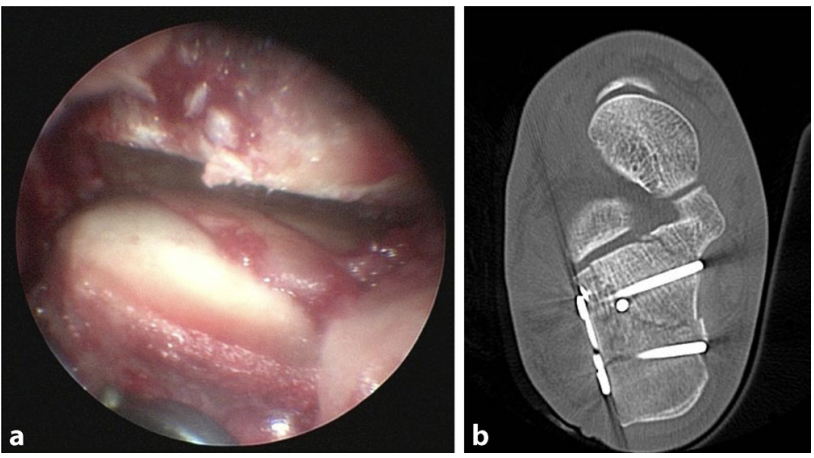

采用 1.4mm 或 1.6mm 克氏针进行临时固定,通过侧位透视与Broden位透视检查复位效果,亦可根据需要采用关节镜直接检查关节面的对合情况,在后足内翻应力下可获得充足的关节显露视野。

对于 SandersⅢ 型或 Ⅳ 型复杂粉碎性骨折,若存在一个或多个中央关节骨块,可采用由内向外逐步重建的方法:从外侧向内侧钻入一枚双头尖克氏针,使克氏针外侧端与骨折面平齐,无针尾突出;外侧骨块复位后,将克氏针从内侧向外侧逆行钻出,贯穿固定外侧骨块。

部分病例中,如关节内骨折线走行不规则,需对移位骨块进行离体重建:将中央关节面骨块与外侧关节骨块取出,在无菌手术台上清理骨块,在直视下完成解剖复位,随后将重建后的关节骨块重新置入术区,精准贴合恒定骨块进行复位。该技术即使对于显露困难或不稳定的骨折块,也能实现可控、解剖学的关节面重建。

术中遗失的的克氏针/螺钉技术也可用于距下关节后关节面的逐步重建,以固定关节面骨块间的碎骨块,实现精准复位;但此类材料若需取出,易造成较大的骨皮质损伤,取出难度较高。复位时推荐使用 1.4mm 和 1.6mm 克氏针,置入前可用侧切刀在克氏针上制作预定折断点,置入后通过轻柔的摆动动作将克氏针在预定点折断,使针尾与骨面平齐,无突出。

步骤 4:内固定稳定

根据关节内骨折块的大小,选用 2.0~3.5mm 拉力螺钉进行固定;最终固定主要采用外侧锁定钢板内固定,微创入路手术中,亦可使用大骨折块螺钉将跟骨结节骨块固定于关节骨块或跟骨前突。